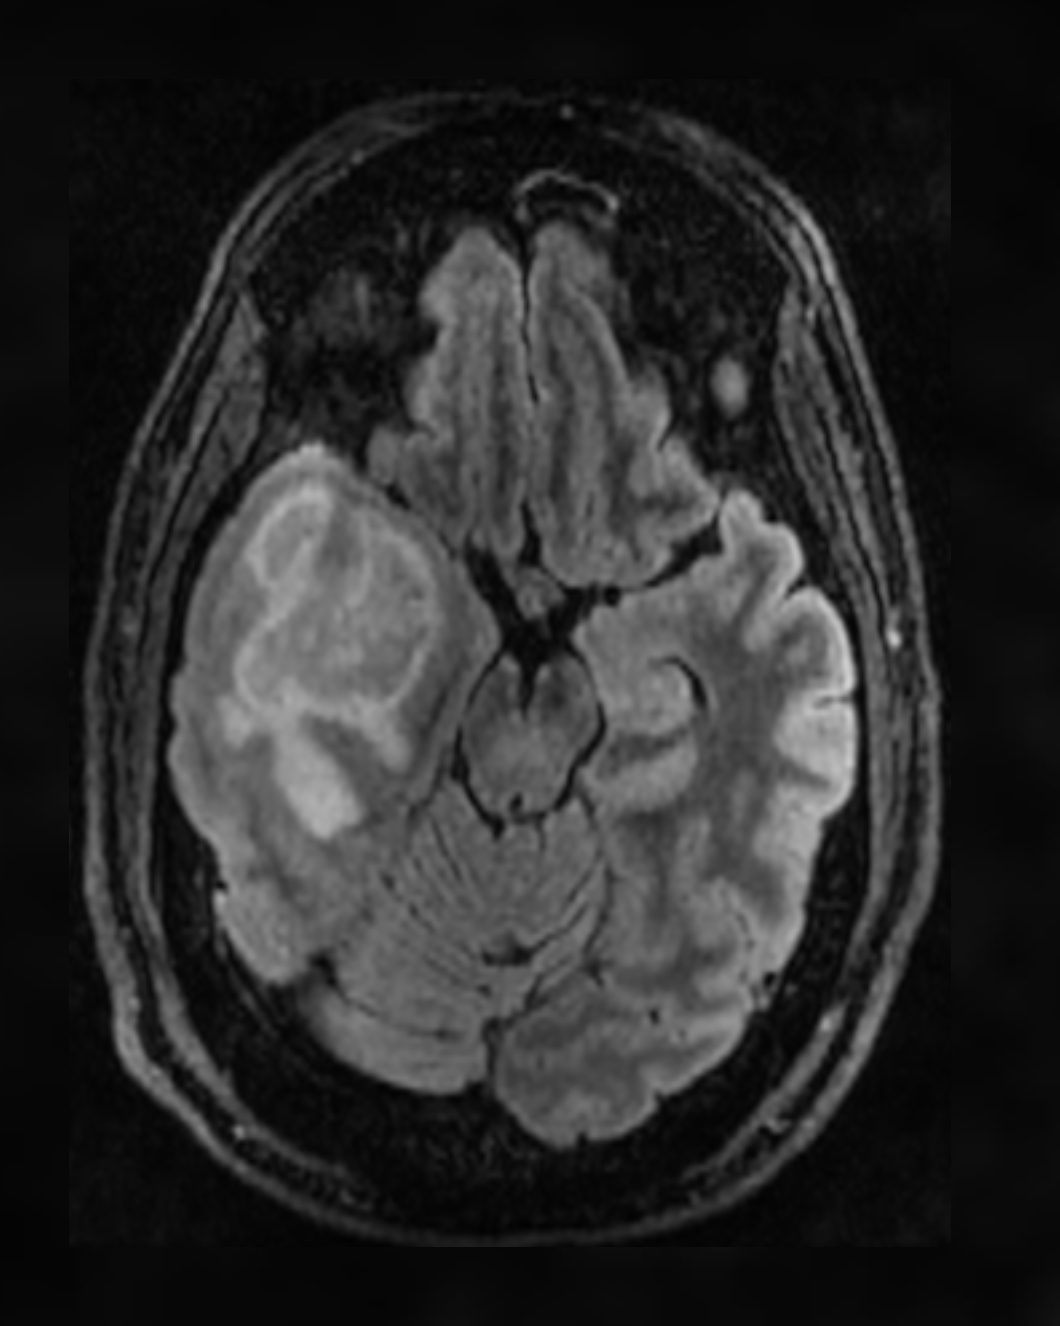

Glioblastoma MRI scan

New Focused Ultrasound Clinical Trial for Recurrent Glioblastoma